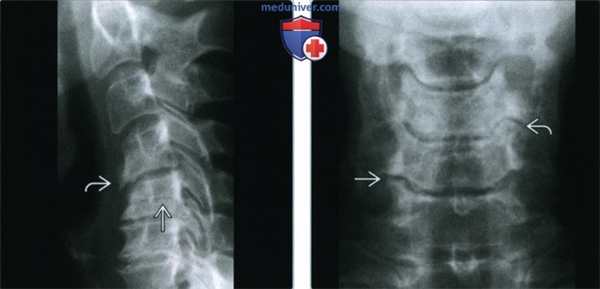

(Слева) Рентгенография в боковой проекции: характерные признаки остеоартроза (ОА) шейного отдела позвоночника с передним спондилезом на уровне дегенератично измененного диска. Остеофиты, сформировавшиеся в апофизарных суставах, часто имеют вид участка просветления, пересекающего тело позвонка. Эти участки просветления распространяются поразительно далеко кпереди.

(Справа) Рентгенография в ПЗ проекции: признаки ОА апофизарных суставов у того же пациента, наиболее выраженные справа на уровне С5-С6 и слева на уровне С4-С5. Эти уровни, наряду с уровнем С6-С7 поражаются наиболее часто.